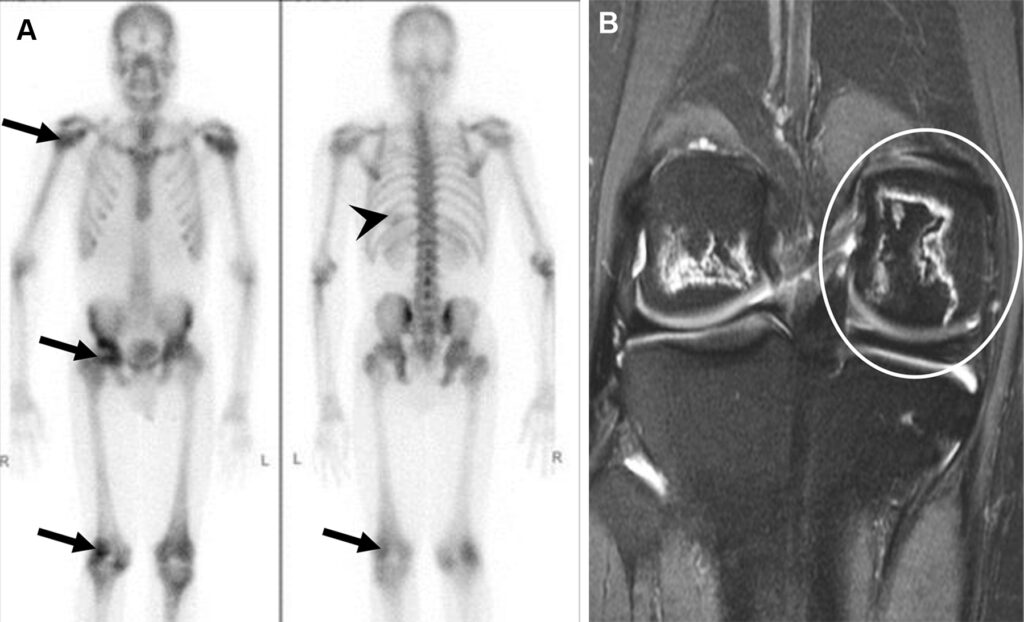

Necrosi avascolare in una donna di 22 anni con anemia falciforme e dolore osseo multifocale ricorrente.

Captazione disomogenea (“a chiazze”) a livello delle epifisi, espressione dei processi di necrosi ischemica ossea (e successiva riparazione) conseguenti alle crisi vaso-occlusive. Si evidenzia inoltre accumulo anomalo del tracciante nell’ipocondrio sinistro. Questo reperto è il segno clinico dell’autoinfarto splenico (milza funzionalmente asplenica e calcificata/sclerotica), una complicanza cronica classica dell’anemia falciforme.

La risonanza magnetica documenta il patognomonico segno della “doppia linea” (double-line sign) a carico del ginocchio nelle sequenze T2. La linea interna (iperintensa) corrisponde al tessuto di granulazione iperemico di riparazione, mentre la linea esterna (ipointensa) rappresenta il vallo di osso sclerotico che delimita la necrosi dall’osso sano.